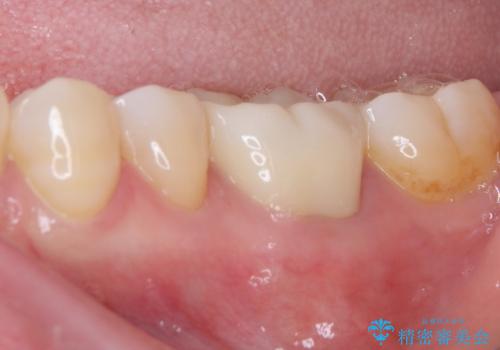

まずは根管治療を行い、症状が落ち着いたことを確認して、オールセラミッククラウンにて補綴治療を行うこととしました。

処置後、下顎の膿の出口はすぐに消えましたが、レントゲン写真からも分かるとおり、歯根途中に穴が開いており、充填材が歯根外にはみ出していました。数ヶ月経過を見たところ、特に異常は認められなかったため、補綴治療を行いました。